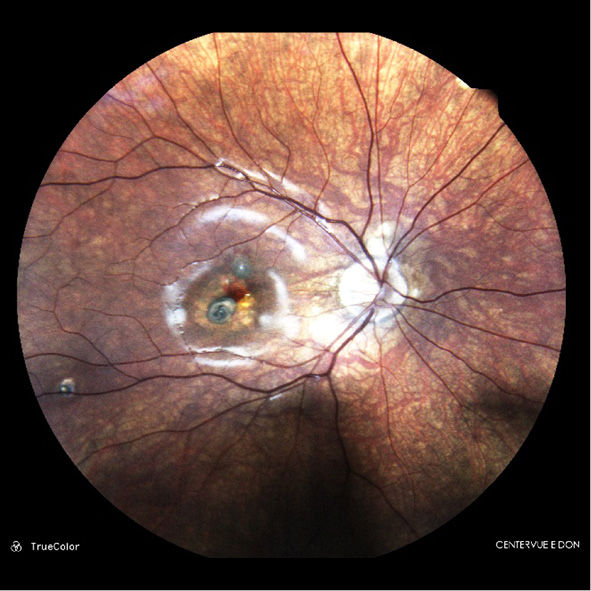

CNM was active in all children. The clinical presentation varied depending on the underlying disease. For example, a grayish subretinal focus with indistinct contours and perifocal hemorrhage, or without hemorrhage, was observed in the chorioretinal/choroidal focus area (Fig. 1). In addition, osteoma (Fig. 2) or hamartoma, and dystrophic changes in the macula in Best’s disease, were observed. Patients with myopia (Fig. 3) and idiopathic forms presented with isolated grayish or yellowish foci with indistinct contours and perifocal hemorrhage, or without it. Juxtapapillary CNM was characterized by the formation of a grayish proliferating focus adjacent to the optic disc (Fig. 4).

Fig. 1. Ophthalmoscopic picture of an active choroidal neovascularization (arrow) in a child with central chorioretinitis of unclear etiology in remission.